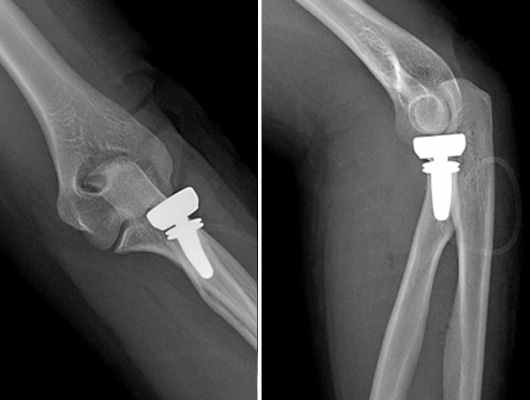

Во время операции подобран компонент максимально точно повторяющий размеры собственной головки лучевой кости (рис. 5, рис. 6).

![]() | ![]() |

На контрольных рентгенограммах положение компонентов эндопротеза удовлетворительное (рис. 7).

На следующий день после операции пациентке разрешены пассивные движения в локтевом суставе. Достигнут полный объем движений. После снятия швов пациентка приступила к обычной, повседневной деятельности, вышла на работу.